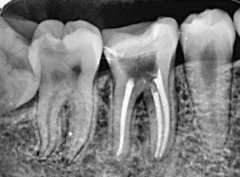

重庆根管治疗哪里用热牙胶?附热牙胶与冷牙胶区别

重庆根管治疗哪里用热牙胶,许多人都想要了解和咨询一下,因为根管治疗项目已经成为了临床工作中的一个特色项目,能够让整个人的口腔状态更加的健康,也能够恢复到正常的口腔

根管治疗的牙齿是什么颜色?根管治疗需要多久完成科普

聊起根管治疗,想必很多朋友都不陌生,毕竟现在大家对口腔健康问题都比较注重,当牙齿出现问题的时候,必要的情况下,需要通过根管治疗来解决,可能对于部分朋友来讲,对根管

根管治疗的牙齿算什么牙?附根管治疗需完成次数科普

牙齿问题是现实生活中不容忽视的一个问题,一旦当牙齿出现问题的时候,无论大问题还是小问题,都会或多或少影响到一个人的生活质量,所以多数情况下都需要进行积极治疗,比如

根管治疗的牙齿可以堵上么?根管治疗技术成熟/附注意事项

根管治疗的牙齿可以堵上么?说起根管治疗,想必大多数朋友都比较熟悉,但是也不乏有一些想要深层次了解根管治疗的朋友们,究竟根管治疗的牙齿可以堵上吗?根管治疗是治什么疾病